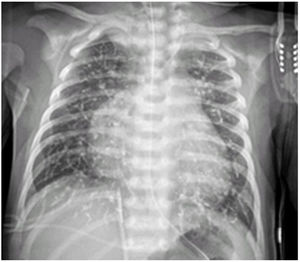

Se realiza una embolización urgente con coils a los 7 días de vida y una segunda embolización con cianoacrilato (Glubran®, cola quirúrgica) a los 26 días de vida. A las 2horas presenta cuadro agudo con llanto, irritabilidad, taquicardia y desaturación, precisando opiáceos a dosis elevadas. En control radiográfico se visualiza material radiopaco en vasos arteriales compatible con microembolismo pulmonar por cianoacrilato (fig. 1). Empeoramiento de la insuficiencia cardiaca congestiva e hipertensión pulmonar que precisa milrinona.

Evolución favorable. Estable respiratoriamente con oxigenoterapia en gafas nasales. Los controles radiográficos no muestran complicaciones, persistiendo cianoacrilato en el árbol vascular. Tras 3 días se retiran milrinona y oxigenoterapia.